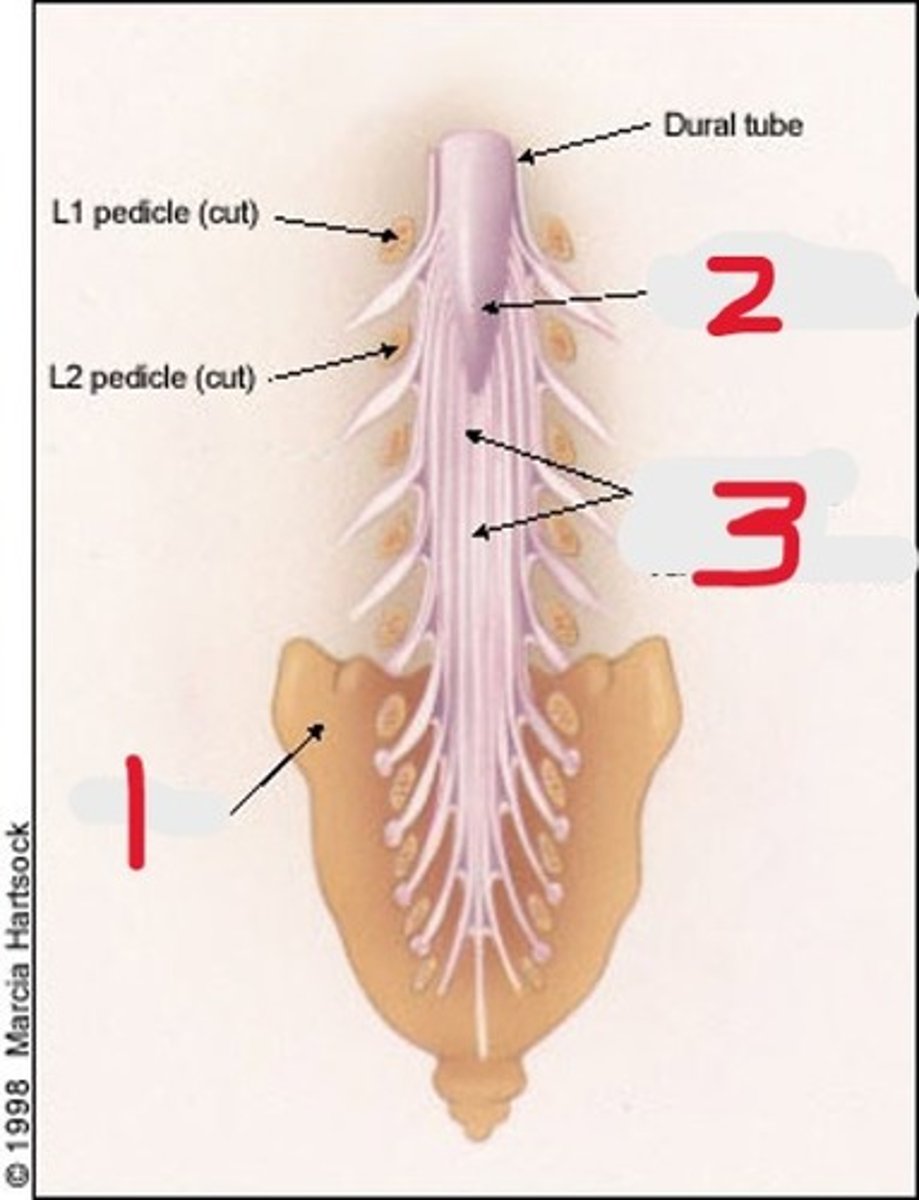

1) Conus medullaris

2) Cauda equina

3) Thecal sac

Name all numbered structures

1) L5

2) Sacrum

3) Conus medullaris

4) Cauda equina

5) Subarachnoid space with contrast

Name all numbered structures

1) Psoas muscle

2) Cauda equina

Name all numbered structures

end of the spinal cord

Where on the spinal cord if the conus medularis found

L1

At what vertebral level is the conus medularis found

L4

The cauda equina tapers into smaller bundles around _____

1) Sacrum

2) Conus medullaris

3) Cauda equina

Name all numbered structures